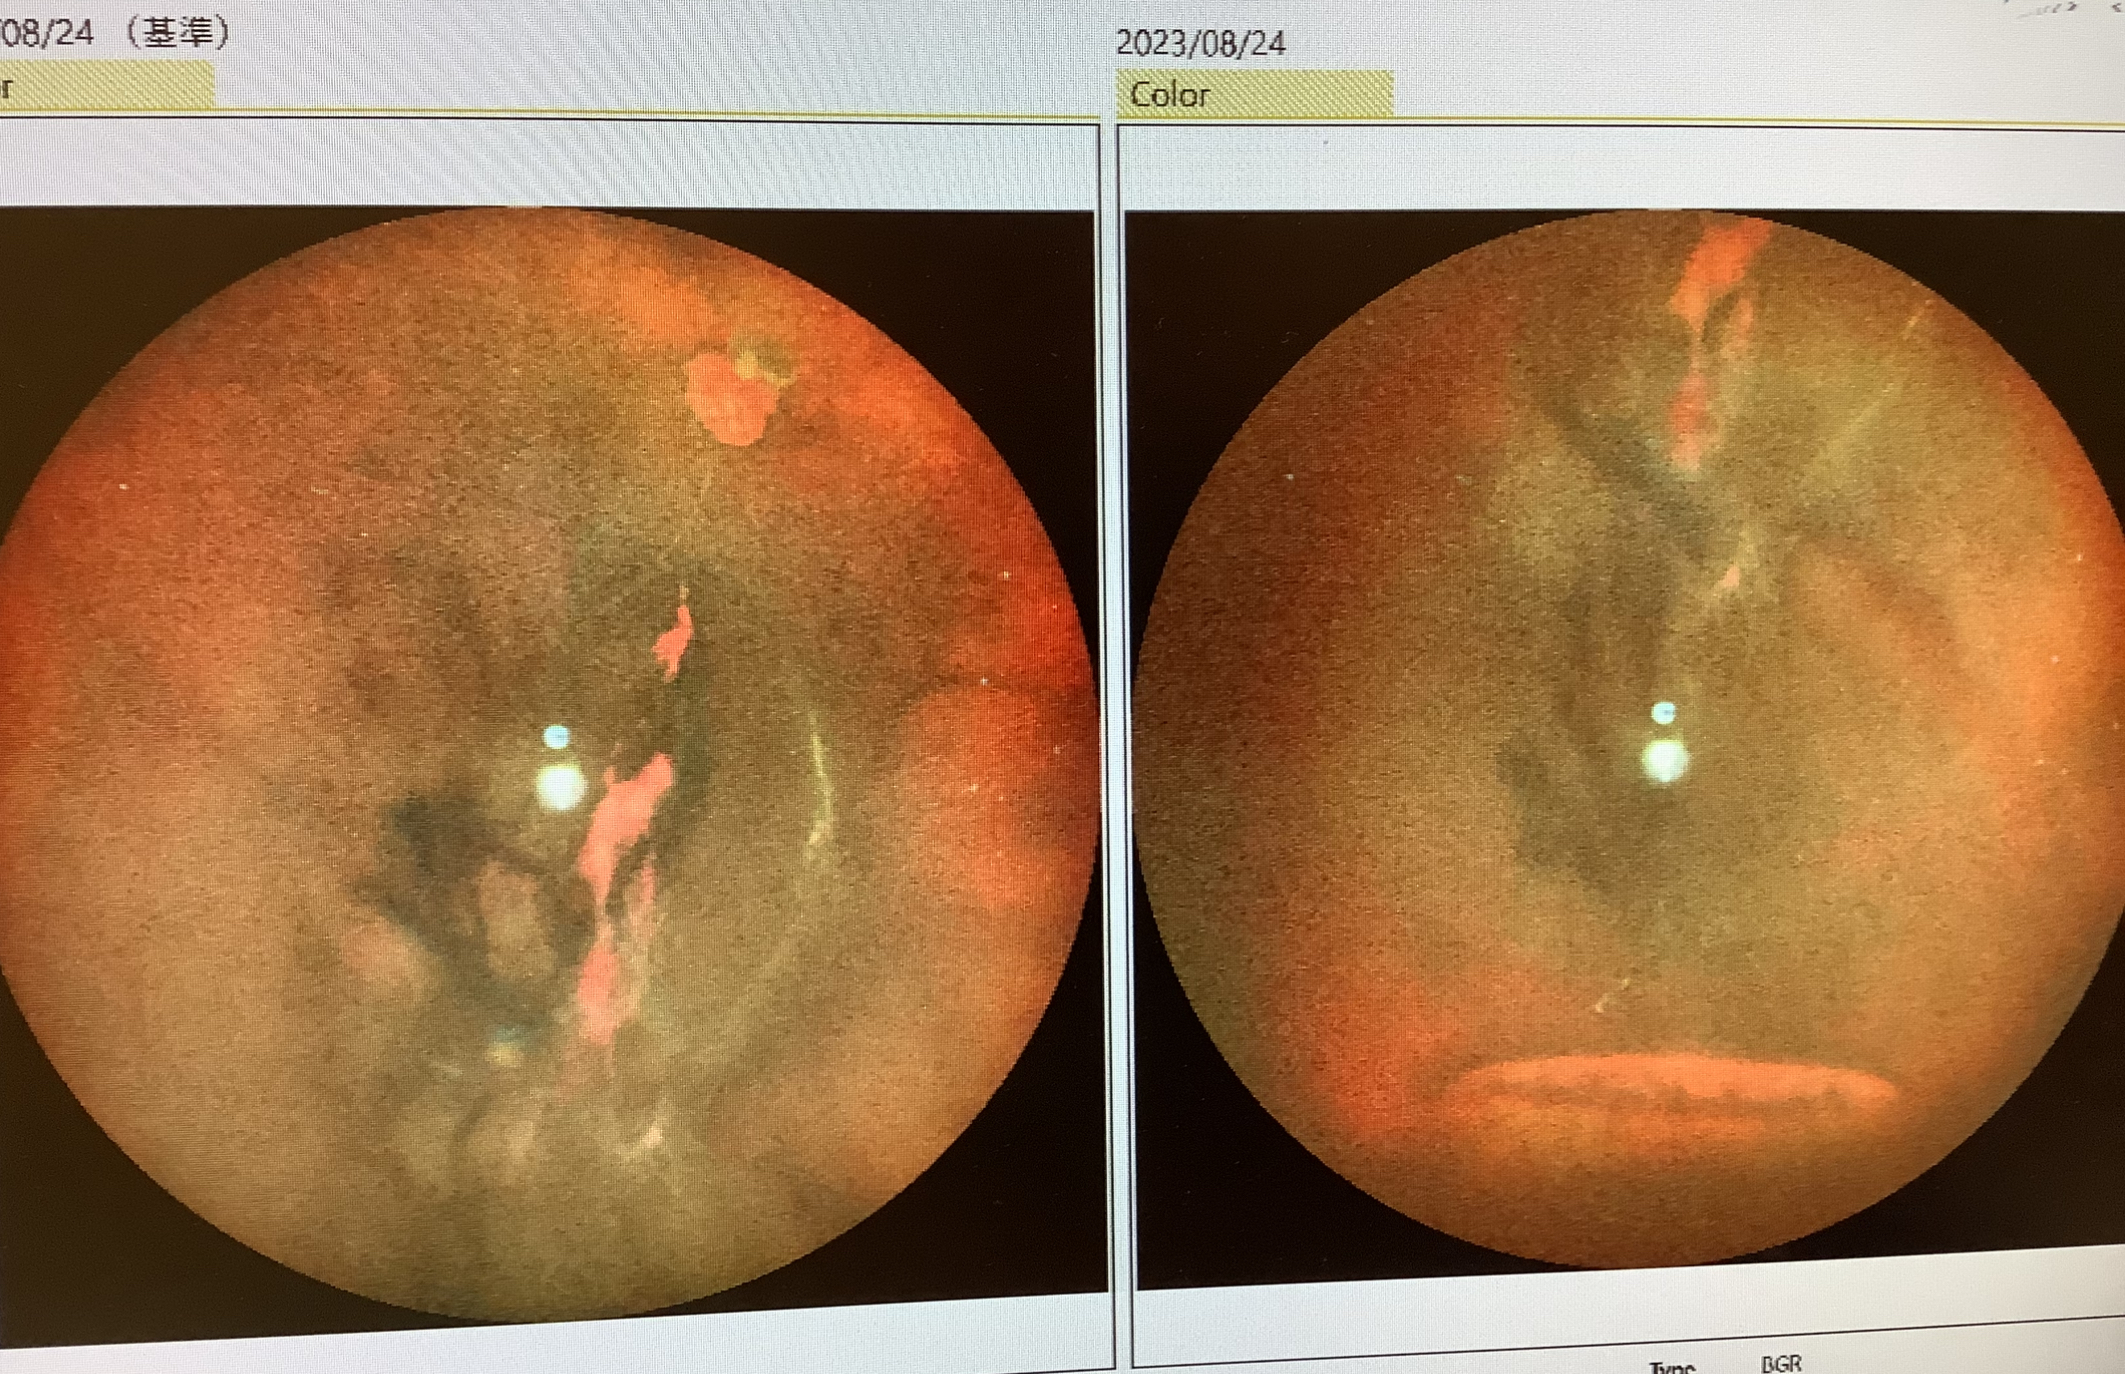

昨日、外来受診された男性は、『1週間前に飛蚊症が出始めて、昨日、急に飛蚊症が強くなり、急激に見えなくなった』といらっしゃいました。1週間前の最初の飛蚊症は“後部硝子体剥離”が起こったことで出てきた症状で、その後部硝子体剥離が網膜を引っ張り、網膜が裂け穴があき(網膜裂孔)、その時に血管も切れて硝子体出血を起こし、急激に視力が低下したと思われました。出血の量が少なく、網膜裂孔がしっかり見えて剥離の範囲が軽度であれば、レーザーで裂孔の周りを固める治療も選択になるのですが、この患者さまの場合、網膜裂孔がギリギリ分かるものの、出血の量が多く、レーザーが届かない状態であったため、硝子体手術で出血を取り除き、網膜剥離も同時に治す方針とさせていただきました。実際の手術では、出血を取り除くと、網膜の剥がれた範囲は軽度で、硝子体腔を空気に換えた後、裂孔の周りをレーザ凝固し、さいごに空気を医療用のガスに換えて手術を終えました。所々、網膜の牽引が強い箇所があり、ここもレーザー治療をしていますが、術後にここが穴となり、網膜剥離が再発することがあるので、注意が必要ですが、なんとかきちんと治ってくれるといいなと思います。